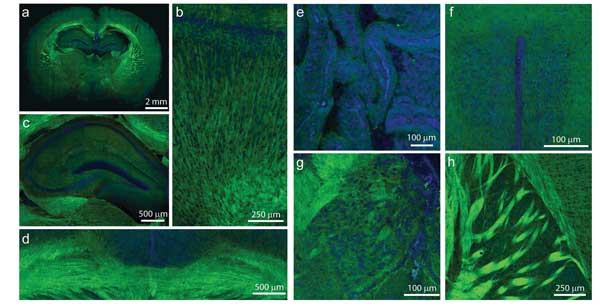

Intraoperative imaging of brain tumors is among the potential uses that could benefit from Raman imaging. Raman imaging has been explored for a range of uses; among the most exciting of these are applications in the biomedical arena. Here, especially in the past decade or so, considerable attention has been paid to the potential of the technique for diagnosis of disease. “One can imagine that Raman would provide something like a chemical histology map,” said Renato Zenobi, a